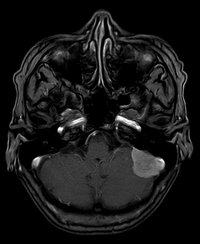

Meningeom

Meningeom - T1 mit KM